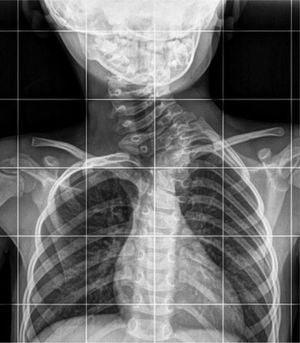

Paciente de 4años que acude a consulta por sospecha de torticolis de años de evolución sin respuesta al tratamiento. En la exploración se observa una giba cervical izquierda, con limitación en el giro y en las inclinaciones, por lo que se solicita la radiografía cervical (fig. 1).

Una hemivértebra es un defecto congénito vertebral poco frecuente debido a una malformación en el desarrollo del núcleo condral de un cuerpo vertebral.

Estos defectos congénitos se asocian a otras malformaciones que debemos buscar sistemáticamente, ya que en muchos casos son inicialmente asintomáticas1,2. Entre estas malformaciones estarían las cardiacas (un 10%), las genitourinarias (un 23%)3 y las anormalidades intraespinales (hasta un 40%).

Su tratamiento puede ser conservador o quirúrgico y su pronóstico es variable, dependiendo del número de vértebras afectadas y de su grado de malformación. Para valorar su tratamiento definitivo es necesario completar estudios con una RMN o una TAC de columna.

No debemos olvidar que ante una torticolis persistente o con escasa respuesta al tratamiento se recomienda solicitar una radiografía para descartar malformaciones vertebrales.